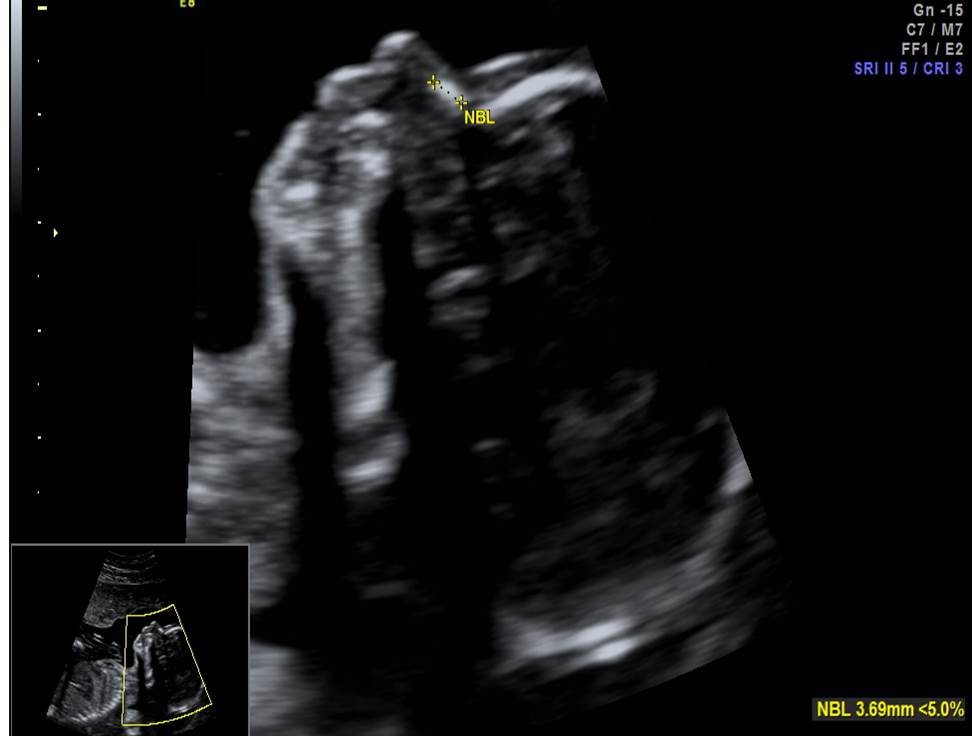

- Проанализируйте изображения плода в 19 недель, есть ли у него какие-либо маркеры хромосомной патологии?

- Необходимо ли рекомендовать инвазивную диагностику? Пациентке 28 лет, в 1 триместре комбинированный риск по трисомии 21 — 1:1220